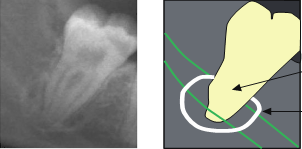

37

impaction of 8s depth?

LL8 - superifical distoangular LR8 - moderate mesioangular

38

impaction of 8 depth?

superficial mesial LL8

39

moderate vertical

40

what other radiographic finding would need to warm pt of here?(not 8)

LR7 – overhang amalgam risk of restoration damage due to proximity, temporise tooth and work on later